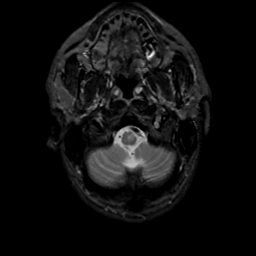

MR Study #16, June 23, 1991 -- Slice #4

[Home][Help][Clinical][Tour 1][Tour 2] Slice 4